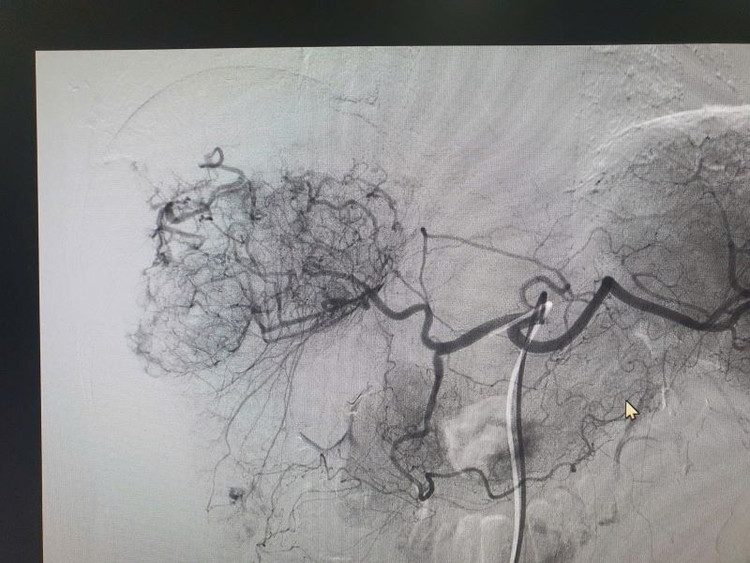

Vỡ u gan chảy máu trước và sau can thiệp - Ảnh BVCC

Kết quả chụp cắt lớp vi tính (CLVT) phát hiện khối u gan phải bị vỡ, có hình ảnh chảy máu đang hoạt động trong ổ bụng. Ngay lập tức, ekip can thiệp của Khoa Chẩn đoán hình ảnh phối hợp cùng các khoa liên quan tiến hành chụp và nút mạch cấp cứu cầm máu khối u gan.

Dưới hướng dẫn của máy chụp mạch số hóa xóa nền (DSA), bác sĩ luồn ống thông vào động mạch gan nuôi khối u, xác định chính xác vị trí chảy máu và tiến hành nút mạch bằng vật liệu chuyên dụng như hạt PVA, keo sinh học hoặc coil kim loại...

Kỹ thuật nút mạch mang lại hiệu quả cầm máu cao, ít xâm lấn, thời gian hồi phục nhanh và đóng vai trò quan trọng trong điều trị cấp cứu khối u gan chảy máu. Sau can thiệp, bệnh nhân được theo dõi sát và đánh giá lại để tiếp tục điều trị bệnh lý nền như hóa trị, nút mạch hóa chất (TACE), hoặc phẫu thuật triệt để nếu đủ điều kiện.)